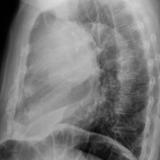

Case 8b Thymoma Lat

Date: 03/27/2009

Views: 14175